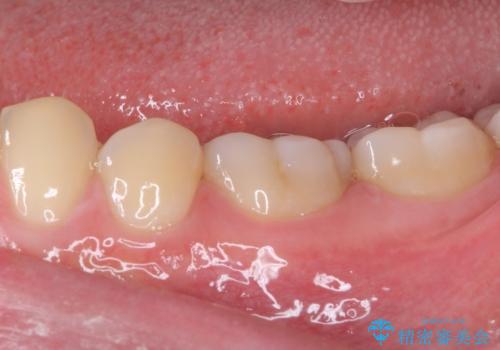

虫歯除去後に痛みは収まり、神経も保存することができました。

変色していた歯もセラミッククラウンで自然な色合いとなり、患者様には大変満足していただきました。